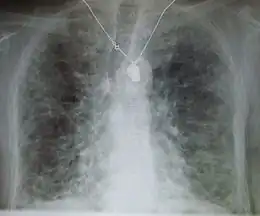

Description de cette image, également commentée ci-après

radiographie du thorax montrant une fibrose pulmonaire.

La radiographie du thorax peut être normale ou anormale, et le scanner thoracique montre fréquemment des anomalies caractéristiques[2].